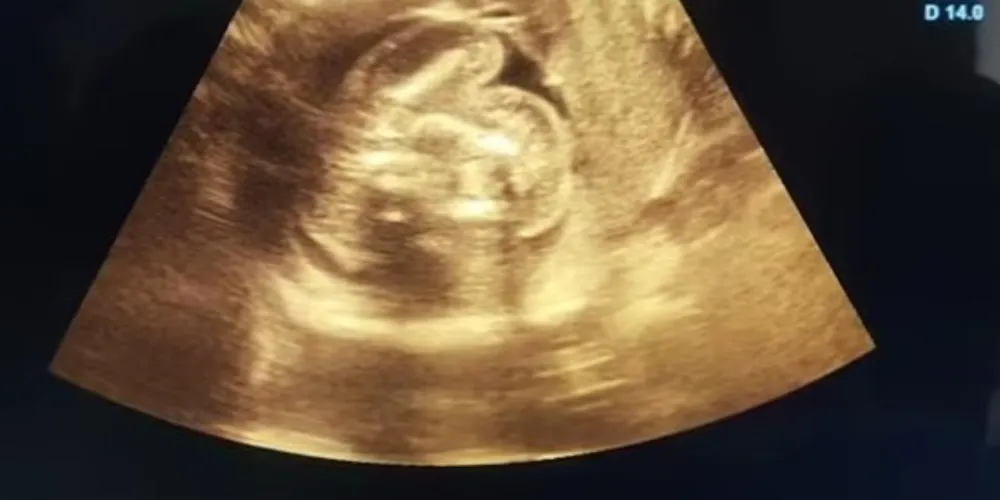

Uma mulher indiana, de 32 anos, foi surpreendida na 35ª semana de gestação ao descobrir que o bebê dela tinha outros dois fetos crescendo dentro do abdômen. O caso, extremamente raro na medicina, foi relatado por médicos do Buldhana Women’s Hospital.

A condição, chamada de “feto dentro de feto”, ocorre quando um embrião se desenvolve do corpo do irmão gêmeo. O fenômeno, documentado apenas cerca de 200 vezes em estudos científicos, tem poucos registros envolvendo múltiplos fetos, como o caso indiano.

O parto ocorreu em 1º de fevereiro. Logo após o nascimento, os obstetras removeram os dois fetos do abdômen do bebê. Segundo a equipe médica, eles pararam de crescer em algum momento da gestação e não apresentavam órgãos vitais completamente formados. Tanto a mãe quanto a criança passam bem.